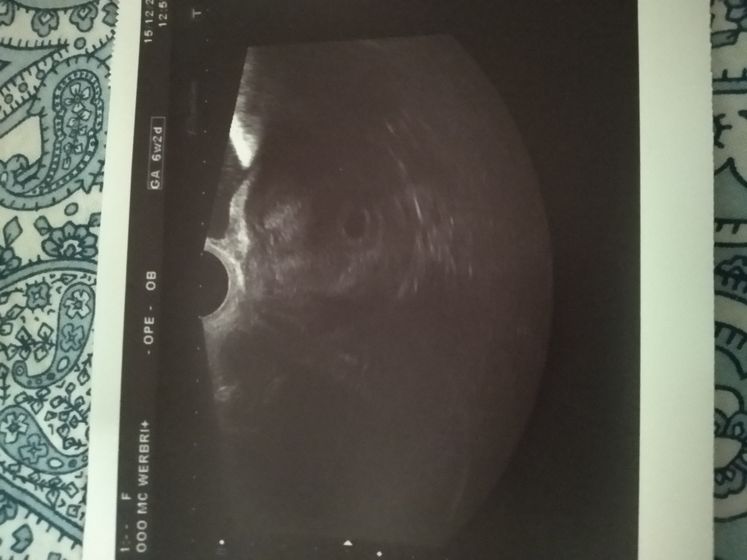

Я была уверена, что уже услышат сердце.Срок был вчера 6 недель 3 дня.В прошлую беременность Димкино сердце на этом сроке уже было.А тут даже эмбрион не увидели ((Хоть и врач сказала, что это нормально, что все есть, все там где должно быть.Желтое тело в яичнике, в матке желточные мешок 2,5 мм.Я понимаю что это беременность, но почему не увидели эмбрион то?(((Расстроилась в общем… пойду через 2 недели ещё раз.Но ждать эти две недели мне будет нелегко.Ходила с мужем и сыном, когда вышла из кабинета сын сразу ко мне-мама, как там Ребёночек? Так мило??Муж разглядывал фотку… эта точка это он да? Это же уже он там? Все в порядке? А я что скажу? Молча дала прочитать заключение.Ехали домой тоже молча.Муж накупил вкусняшек, а меня воротит от всего просто.Вот как то так… вроде ничего плохого не сказали, а осадочек остался…

ПЯ маленький для такого срока, очень странно